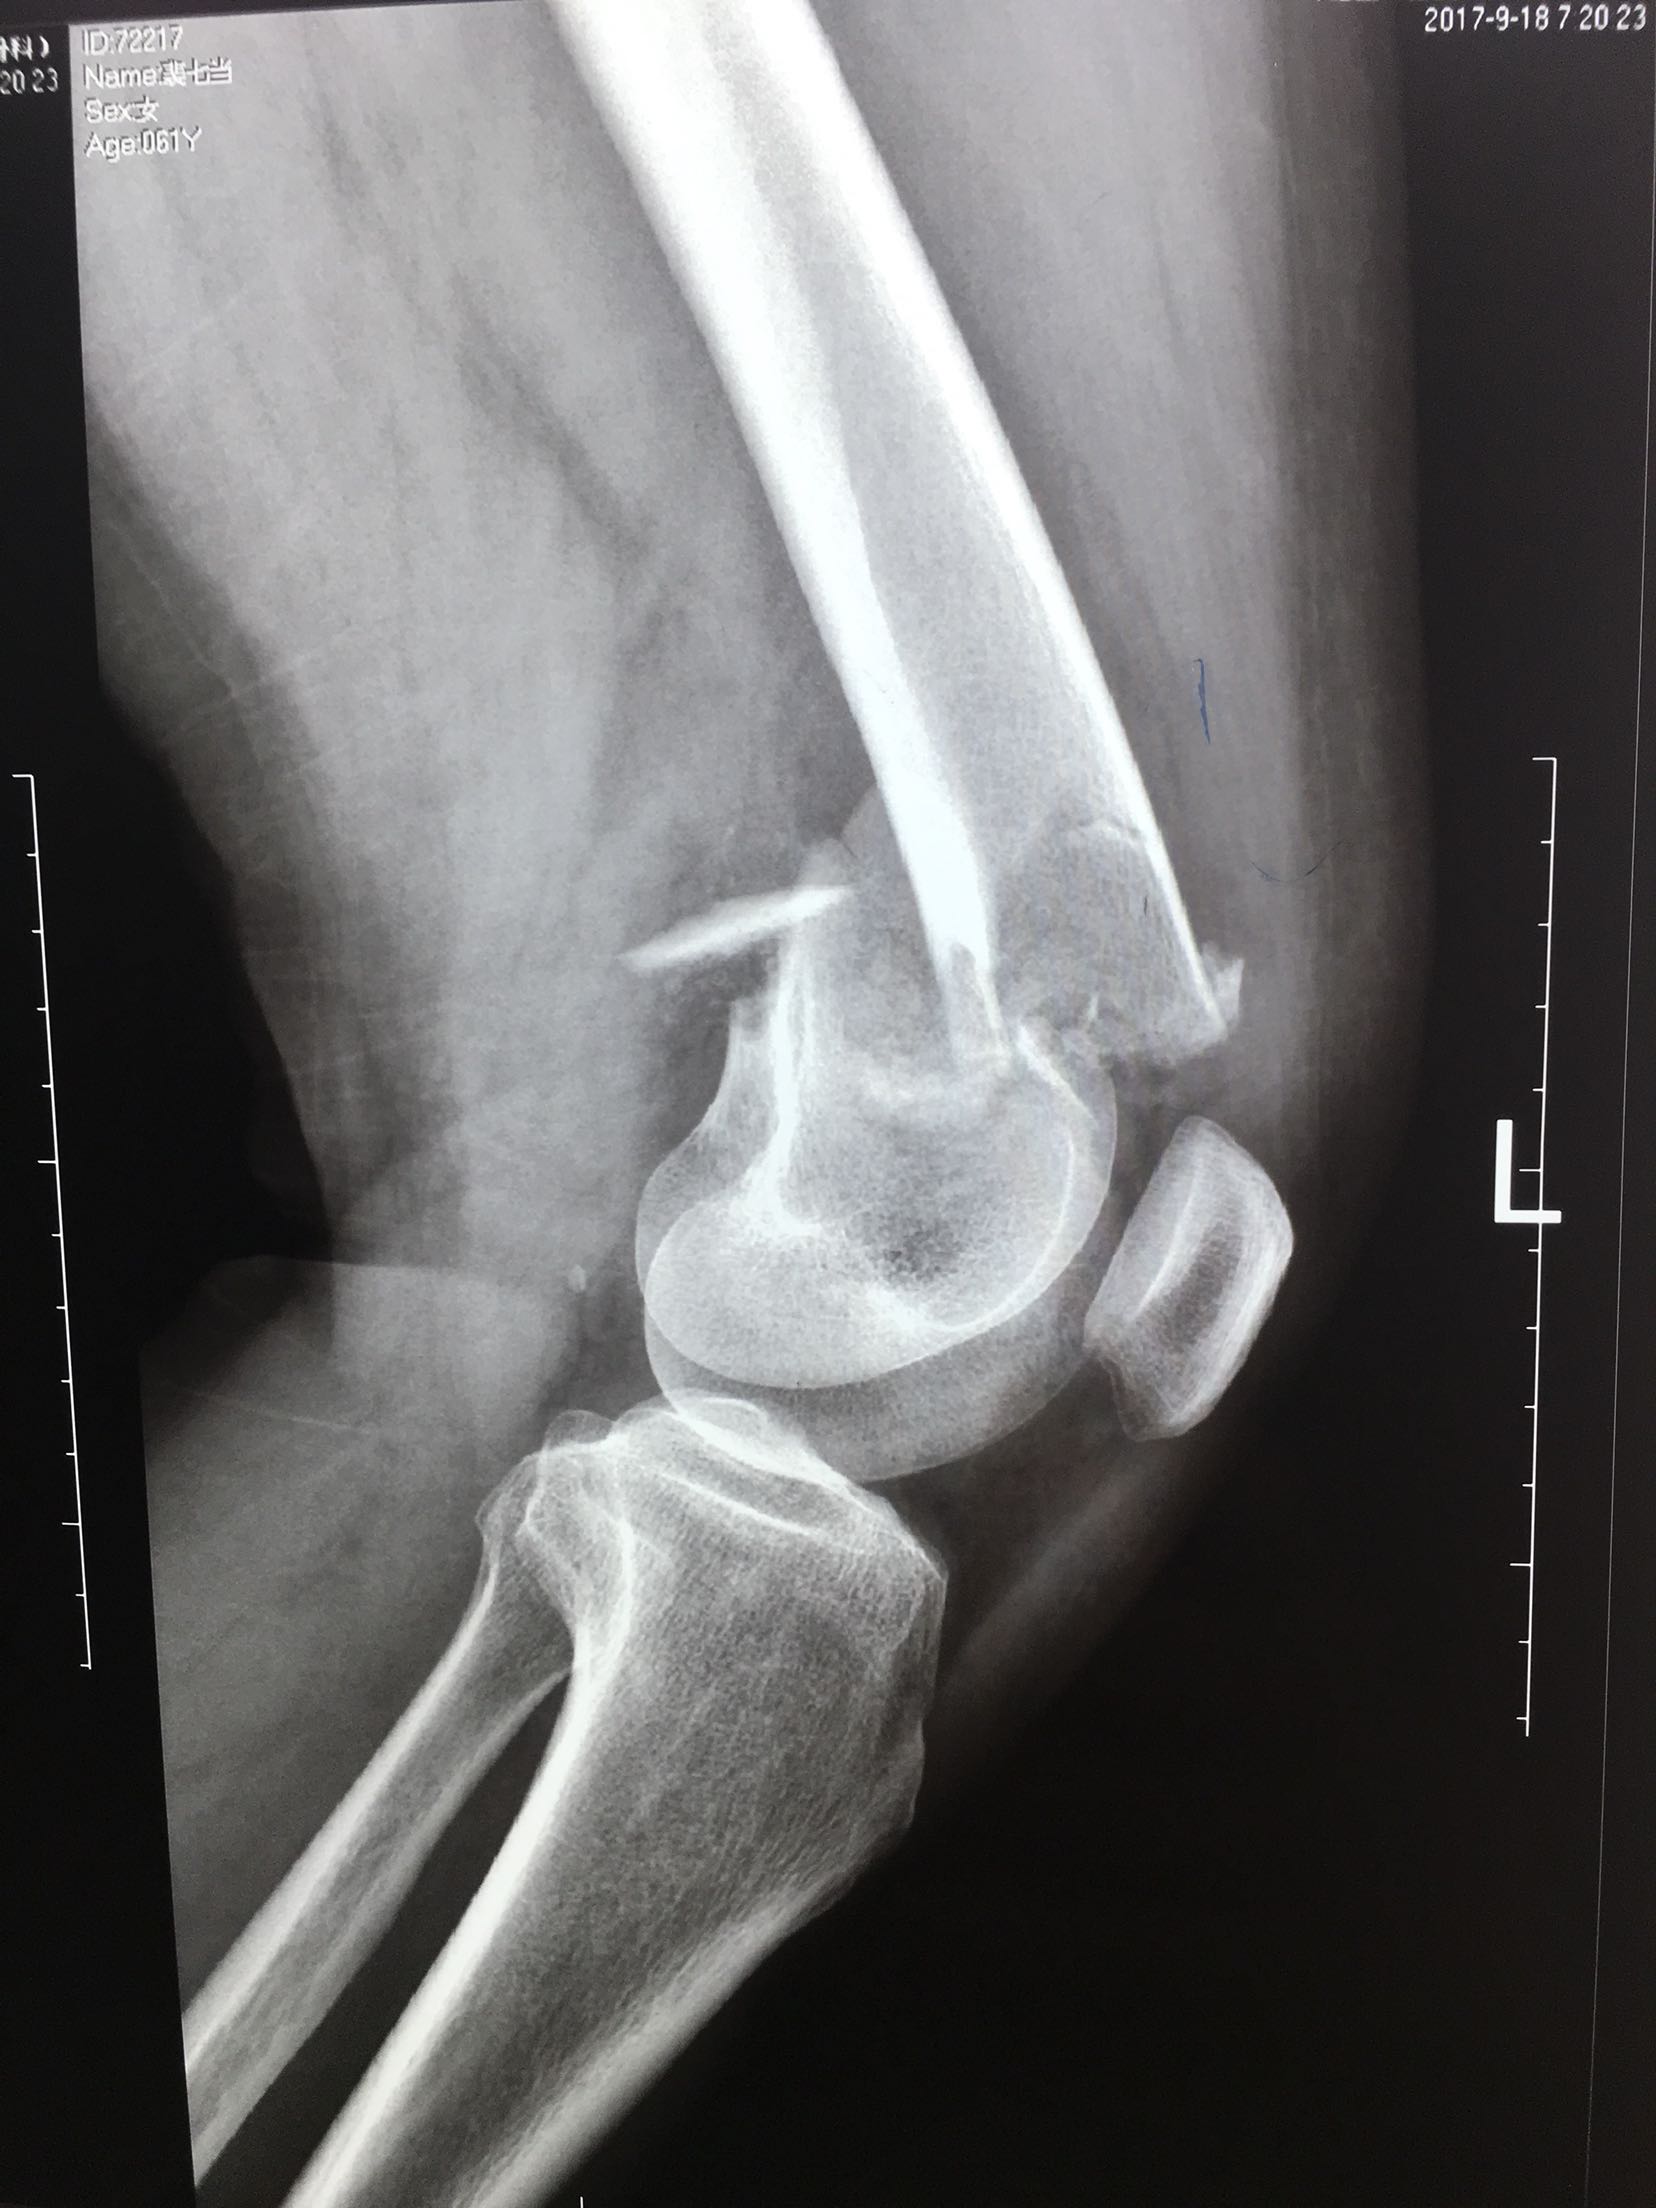

股骨髁上骨折

患者,女性,61岁,摔伤后左大腿疼痛,畸形,活动受限1小时。

左大腿远端局部肿胀,环形压痛,可及骨檫音,异常活动,

远端血运感觉正常。

完善检查,急诊在局麻下行胫骨结节骨牵引术。术后一周,病情平稳,在腰麻下行切复内固定术,考虑骨折粉碎,骨质疏松,拟行双钢板固定。术后抗炎,对症治疗,嘱咐一周后早期膝关节微动锻炼。